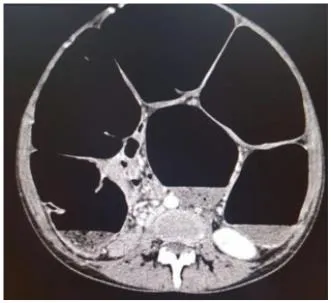

U-shaped, distended sigmoid colon, a haustral collection of gas

⇒ extending from the pelvis to the right upper quadrant

Only 60% of patients